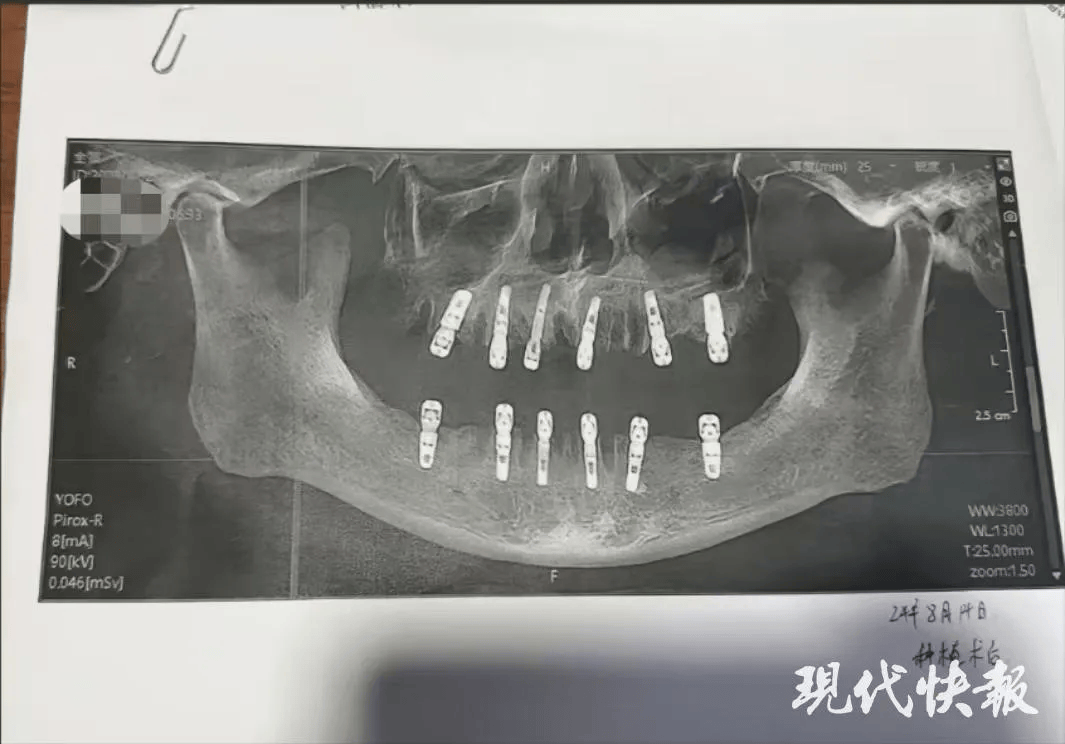

舒女士的父親黃某8月14日在德維口腔醫院接受牙科手術。根據種植手術同意書顯示,本次治療拔牙23顆、種植牙齒12顆,並且均為即刻修復,即「當天拔、當天種」,負責進行治療的醫師為袁某。

然而,據黃某的種植手術同意書,在其接受的手術中,有多顆臼齒在拔除當天就進行了種植,與工作人員所介紹的不符。